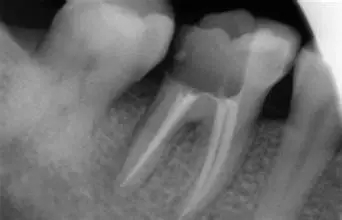

深圳愛康健口腔醫院醫生表示蛀牙也並不是直接就能從(cong) 口中直觀的看出蛀牙的嚴(yan) 重程度的,因為(wei) 很多表麵上看隻有一個(ge) 很小的黑色斑點,但是裏麵被蛀掉的牙齒組織多,所以不能隻憑肉眼來進行判斷的,需要通過拍片來精準的評估,才能保障補牙的結果。

一般來說,比較輕微的齲壞,臨(lin) 床經驗豐(feng) 富的補牙醫生一般是不用拍片子的,很直觀就能看到大致的症狀,但是也有意外的情況,還有對於(yu) 齲壞較深一般情況比較複雜,需要拍片子來確認齲壞程度、麵積大小,以及是否傷(shang) 害到要牙神經和牙根尖組織等。

再者說,如果是已經傷(shang) 害到牙神經的情況,如果需要根管治療,是一定要拍片子的,需要清晰的片子來指導完成顯微鏡下根管治療。而且有的嚴(yan) 重的齲壞,做根管治療一般是需要拍幾次牙片的,比如在治療前,以及每一次複診都是需要拍片查看根管治療的結果的,隻有嚴(yan) 格監督結果,才能保障補牙的結果,所以補牙拍牙片是必要的。